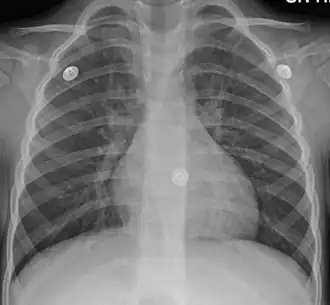

Figure A shows the location of the lungs and bronchial tubes. Figure B is an enlarged view of a normal bronchial tube. Figure C is an enlarged view of a bronchial tube with bronchitis. | |